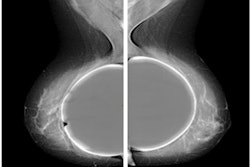

"Implant rupture is an important complication of breast augmentation performed for several reasons, including reconstruction post-mastectomy and cosmetic enhancement," radiology registrar Dr. Madiha Hussain and colleagues at University College Hospital noted in an e-poster.

"Implant rupture can be intracapsular or extracapsular, depending on the location of the ruptured silicone/saline in relation to the fibrous capsule," they explained.

The group evaluates the accuracy of ultrasound versus MRI in the diagnosis of breast implant rupture by conducting a retrospective analysis of patients who underwent an initial ultrasound scan followed by a breast implant MRI protocols exam between April 2019 and September 2022.